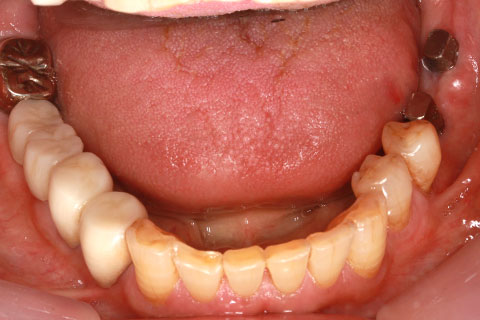

• 症例2

治療前

インプラント埋入時

治療後

年齢・性別

57歳男性

治療期間

3ヶ月

抜歯

なし

治療費

154万円

備考

左上5.6.7 及び左下6.7欠損

治療内容

左上5.6.7と左下6.7欠損部にインプラント埋入

施術の副作用(リスク)

オペによる知覚障害。インプラントによる歯肉炎。インプラント脱落。